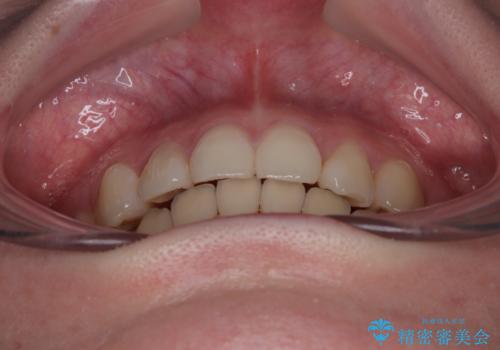

上下の八重歯とクロスバイト ワイヤー装置での抜歯矯正

20歳ということもあり、歯の移動速度が非常に速く、1年強という短期間であっという間に治療を終えることができました。